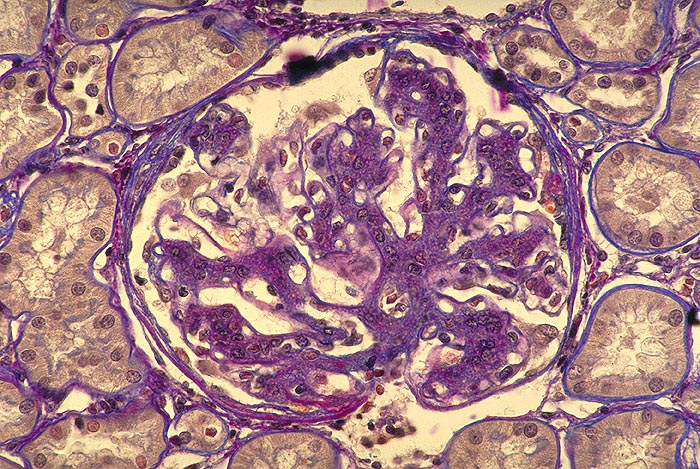

Diffuse Glomerulosklerose bei Diabetes mellitus

Fingerförmige Verbreiterung des Mesangiums ohne gleichzeitige Zellvermehrung. Korbartige Geflechtstruktur der mesangialen Matrix. Keine mesangiale Zellvermehrung. Die peripheren Basalmembranen erscheinen verdickt.

Diffuse Glomerulosklerose: progrediente Verbreiterung der glomerulären Basalmembran und des Mesangiums (ca. 2-5 Jahre nach Diabetesbeginn nachweisbar). Mesangiumverbreiterung bedingt durch Matrixzunahme anfänglich auch von leichter mesangialer Zellvermehrung begleitet. Der Schweregrad der diffusen Glomerulosklerose korreliert am besten mit klinischen Symptomen: Proteinurie, Abnahme der glomerulären Filtrationsrate.